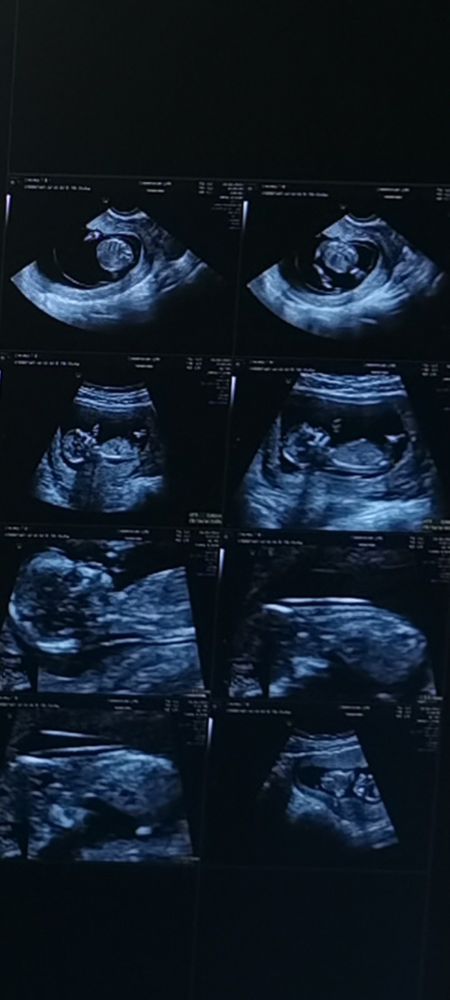

Я вышла, в голове пронеслась куча мыслей, а вдруг какой-то синдром, уже второй врач смотрит, молчат. То ли из-за нервов, то ли из-за таблеток на голодный желудок, меня начало рвать, руки и ноги трястись. Я умылась, села на лавочку и стала глубоко дышать, пытаясь взять себя в руки и успокоится. Немного успокоившись, я вернулась в кабинет. Пришла третья врач, остальные вышли из кабинета. Врач стала вести со мной непринуждённую беседу, я расслабилась, тонус слегка спал и врач смогла завершить осмотр. С малышом все хорошо, никаких отклонений. После узи, мне разрешили сфотографировать монитор❤️ Про пол я даже не спросила.